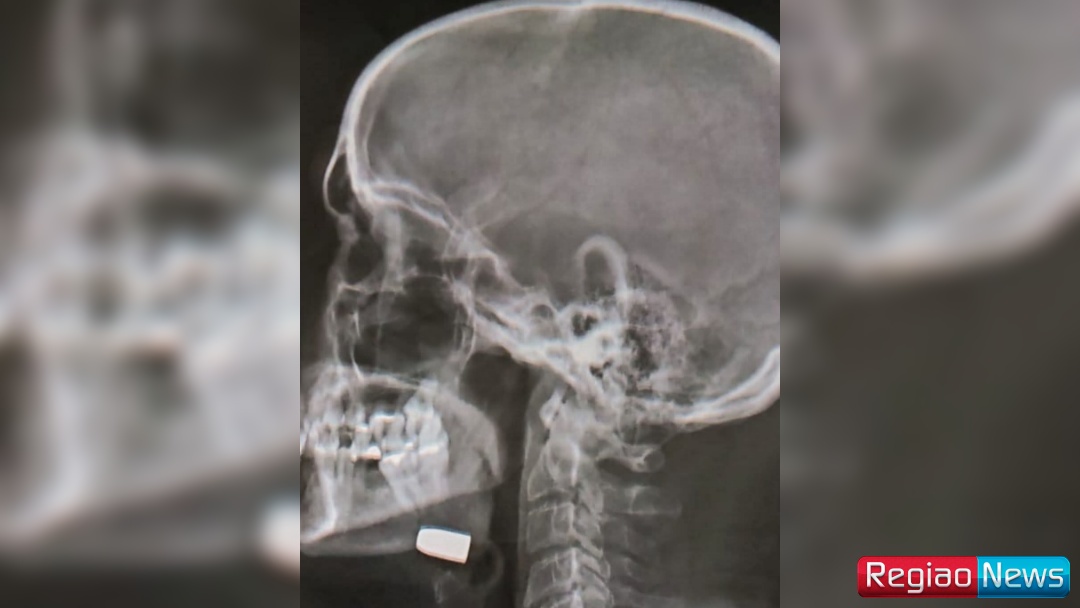

A jovem relatou que, logo após o ferimento, o pastor foi levado à UPA, onde recebeu apenas pontos no local e foi liberado sem a realização de exames de imagem, como um raio-x. “O que mais nos deixou indignados é que, ainda na madrugada do ocorrido, ele procurou atendimento no UPA, recebeu apenas pontos e foi liberado para casa, sem sequer fazer um raio-x — mesmo com a bala ainda alojada”, desabafou.

No período da tarde, devido ao agravamento da dor e à percepção de que o projétil permanecia no rosto, a família retornou à unidade de saúde. Somente então o paciente foi encaminhado ao hospital, onde passou por exames de imagem adequados e teve a gravidade do caso confirmada.